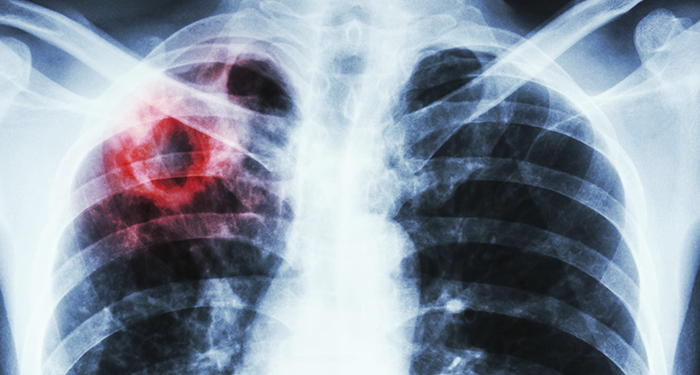

World Tuberculosis Day – March 24, 2019

On this World Tuberculosis (TB) Day, CIHR- Institute of Infection and Immunity reaffirms its commitment to eliminating this deadly disease. TB is both preventable and treatable, yet the global burden of the disease remains high. While the overall rate of TB in Canada is one of the lowest in the world, individuals without access to quality health care, food security, housing and other social determinants of health are among the most susceptible. In Canada, TB disproportionately affects Indigenous Peoples and foreign-born individuals.

TB continues to be among the leading cause of death due to infectious disease globally. We need to accelerate our research efforts to develop better prevention, early diagnosis and treatment methods. CIHR is committed to addressing these needs to improve the health of Canadians and make a difference globally.